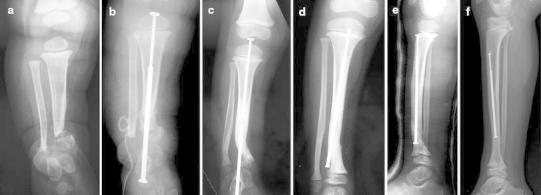

Fig. 2.

Case 2. a Anteroposterior radiograph showing CPT of the distal metaphysis of the tibia in a 10-month-old boy. b Postoperative radiograph of the first stage of the induced membrane technique with cement spacer on the tibia and osteosynthesis with a tibial transplantar telescopic nail. c Dissociation of the two parts of the telescopic nail lead to changing the nail in order to release the tibiotalar joint. d Anteroposterior radiograph after changing the telescopic nail 2.5 years after the induced membrane procedure. e Non-displaced fracture after a trauma 3.5 years after the induced membrane procedure treated by cast. f Radiograph at the last follow-up (8 years)